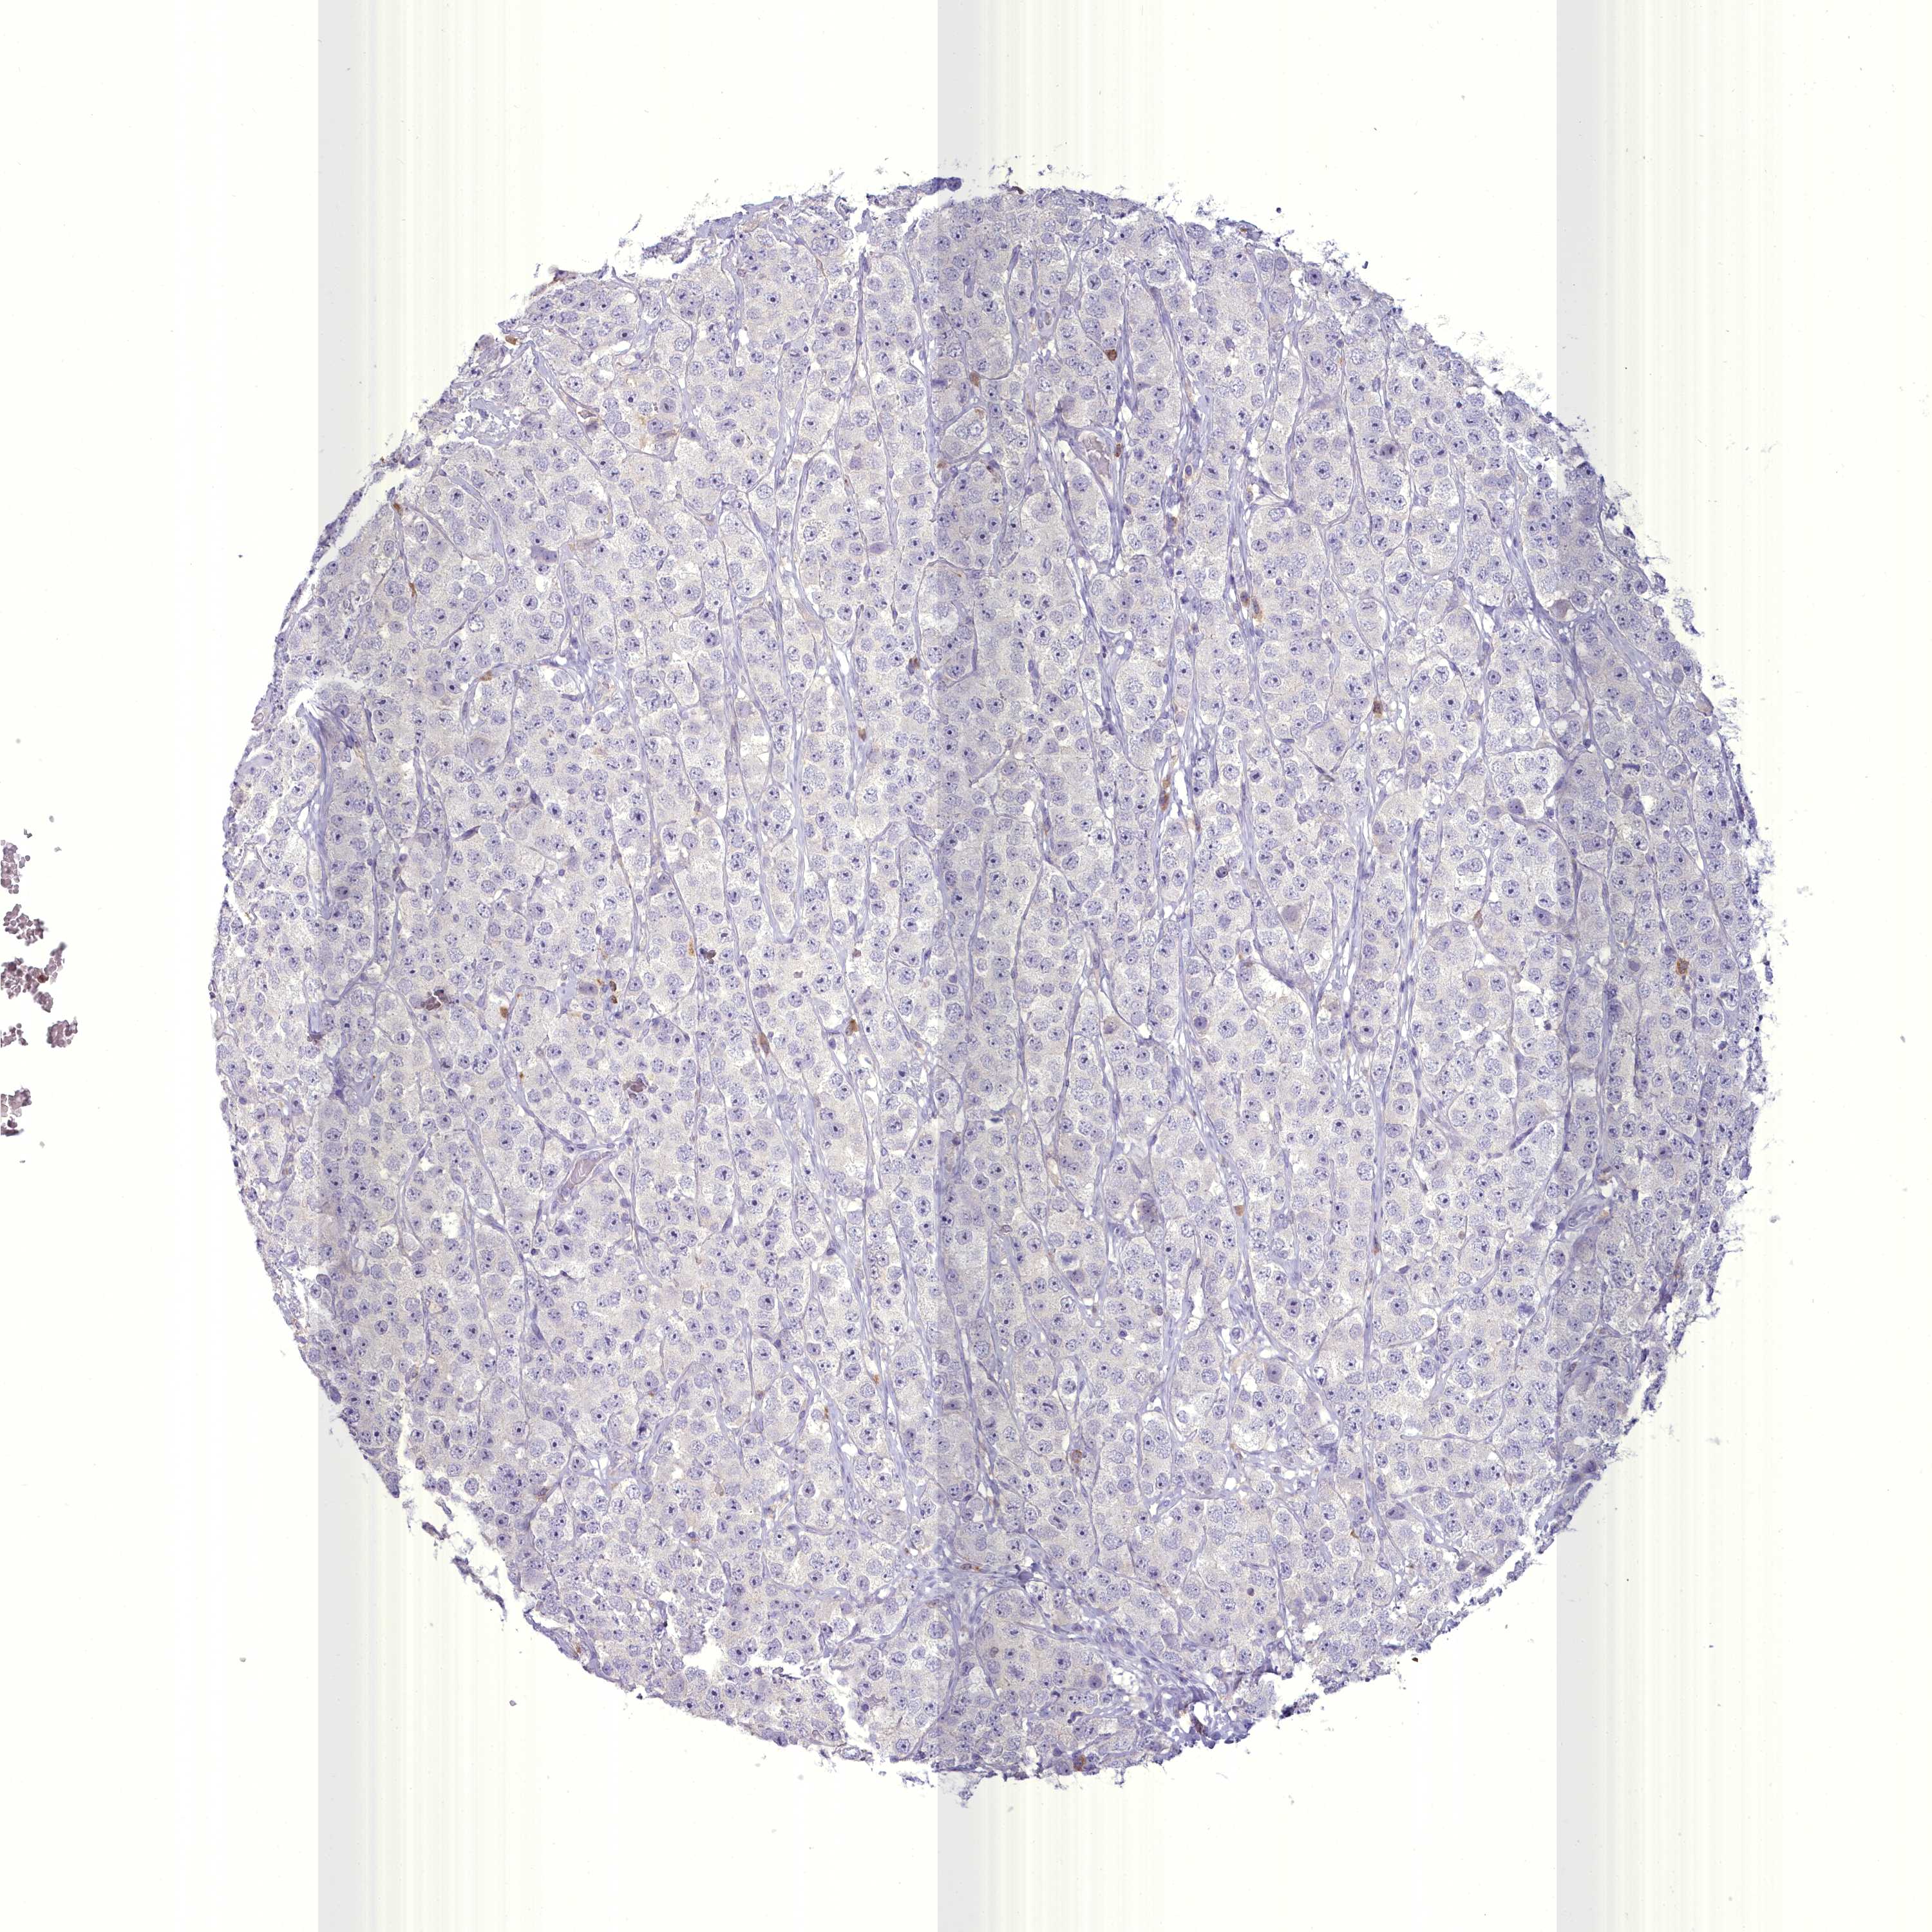

TESTIS CANCER - Protein expressioni

A mouse-over function shows sample information and annotation data. Click on an image to view it in a full screen mode. Samples can be filtered based on level of antibody staining by selecting one or several of the following categories: high, medium, low and not detected. The assay and annotation is described here.

Note that samples used for immunohistochemistry by the Human Protein Atlas do not correspond to samples in the TCGA dataset.

Antibody stainingi

Antibody staining in the annotated cell types in the current human tissue is reported as not detected, low, medium, or high, based on conventional immunohistochemistry profiling in selected tissues. This score is based on the combination of the staining intensity and fraction of stained cells.

Each image is clickable and will lead to virtual microscopy that enables deeper exploration of all samples and also displays staining intensity scores, fraction scores and subcellular localization as well as patient and tissue information for each sample.

Antibody HPA038310

Urothelial carcinoma, High grade

Seminoma, NOS